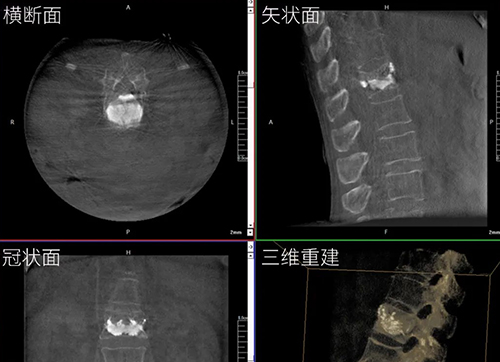

【CAOS2025骨科医师年会】普爱医疗举办骨科手术机器人实操体验活动

第十六届中国医师协会骨科医师年会(CAOS 2025)于2025年6月19日-22日在湖南长沙举行。普爱医疗携骨科手术机器人与骨科影像解决方案亮相,同步开展设备实操体验,邀请骨科手术机器人临床应用专家演示指导,为参会者提...